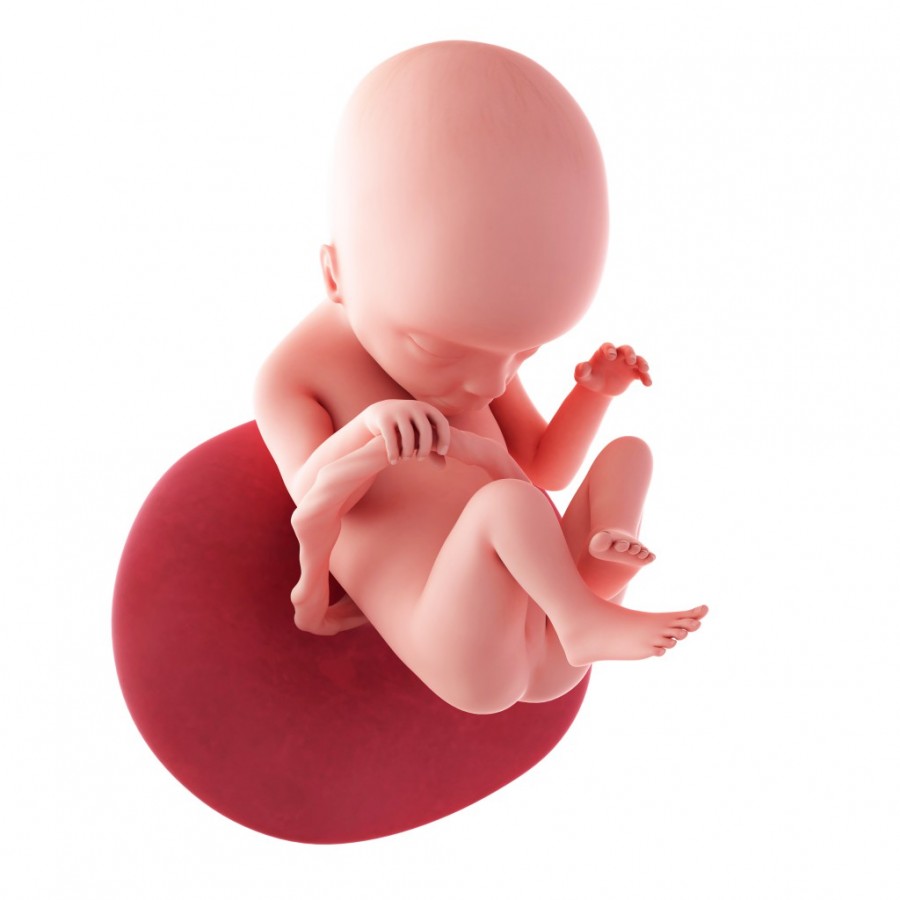

Развитие плода на восемнадцатой неделе беременности

Размер плода в среднем достигает 20 см, вес его равен 200-220 г. На данном этапе развития продолжает формирование нервная система ребенка. В первую очередь растет его головной мозг, на нем появляются первые борозды и извилины. У плода появляются нервы, по которым головной мозг посылает импульсы в различные системы его организма, формируется тимус – важная составляющая иммунной системы человека.

Известно, что на 18 неделе беременности плод активно реагирует на внешние световые раздражители. Он улавливает, где находится мама – в темноте или при ярком дневном свете. При этом глаза будущего ребенка находятся в закрытом состоянии. В целом его органы зрения полностью сформированы.

В этот период времени плод очень активен. Его тело еще легко помещается в матке, ему достаточно места для кувырканий и переворотов, способных доставить маме много новых ощущений.